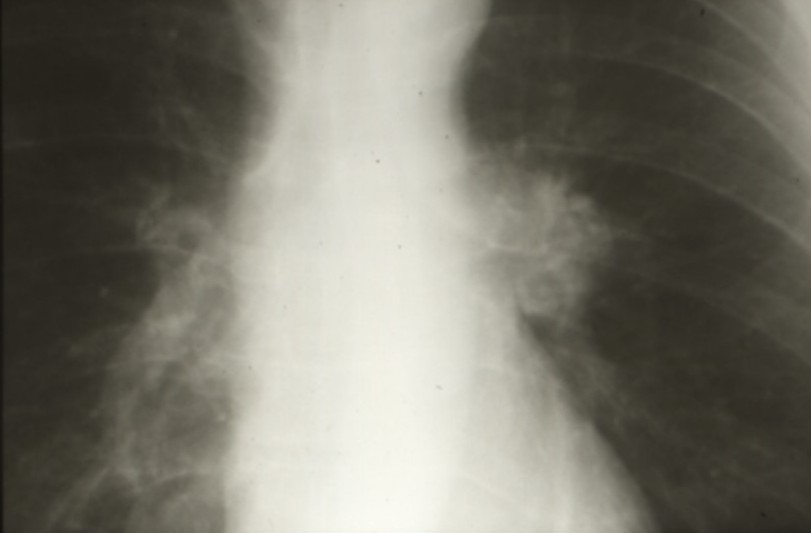

Cancers bronchiques